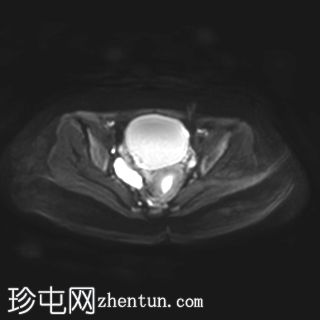

轴位

T1加权像

右侧卵巢增大,卵泡呈周边排列。

附件血管蒂扭转(漩涡征)。

右侧附件旁可见一较大的、边界清晰的盆腔囊性病变,向右倾斜,提示为卵巢旁囊肿。

本病例展示了卵巢扭转的典型影像学特征,包括卵巢增大、卵泡呈周边移位、卵巢向内侧偏移以及特征性的漩涡征。

在这种情况下,较大的卵巢旁囊肿被认为是发生卵巢扭转的高危因素。如果卵巢旁囊肿较大(>5厘米)或活动度较大,其重量/活动度增加会牵拉附件,导致卵巢和输卵管发生扭转。